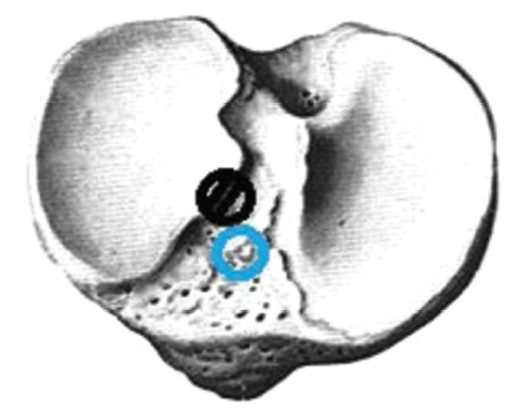

When the primary channel was displaced inwards, the graft was removed, a screw was inserted there, and a new channel with a diameter of 6–7 mm was formed. The screw was inserted to not break the wall of the new channel (Fig. 2).

Fig. 2. The location of the tibial canal inside, — correct channel placement.